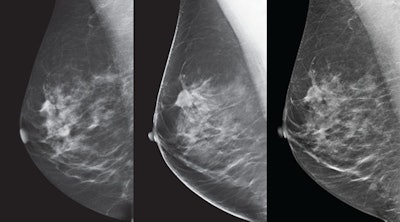

GE Healthcare's SenoClaire tomosynthesis system. All images courtesy of GE Healthcare.

SenoClaire conducts a low-dose short x-ray sweep around the positioned breast, taking nine exposures in a "step-and-shoot" method which removes potential motion from images, because the tube makes a complete stop for each of the exposures. This provides higher peak contrast for microcalcifications than conventional continuous tube motion, according to Singh.

SenoClaire also includes GE's adaptive statistical iterative reconstruction (ASiR) dose reduction technology. ASiR enables the visualization of microcalcifications better than the traditional filtered back-projection algorithms, according to GE.

In addition, SenoClaire's dual-track x-ray tube (made with molybdenum and rhodium) delivers a range of x-ray spectra to penetrate the breast based on breast density and compressed breast thickness, according to GE. The device's automatic optimization of parameters (AOP) technology identifies the densest breast regions and selects the appropriate anode, filter, kV, and mAs to allow for consistent image quality at the most optimal radiation dose.

And it's dose that counts, GE said: A single mediolateral oblique (MLO) view from SenoClaire is comparable to two-view digital mammography, making the exam half the dose with one compression.